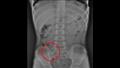

وكشفت فحوصات الأشعة السينية لصدر وبطن الطفل عن وجود قلم رصاص عالق في معدته، لذا أخبره الطبيب بالإكثار من السوائل، ، ولم يسمحوا له بتناول أي شيء سوى الموز لتسهيل عملية إزالة القلم من أمعائه.

أظهرت الأشعة السينية لاحقا أن قلم الرصاص تحرك من المعدة ليصل إلى "اللفائفي الأعوري"، وهو صمام عضلي يفصل بين الأمعاء الدقيقة والغليظة.